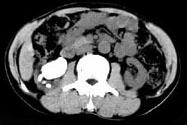

- 多项选择题男,53岁, 反复右侧腰部隐痛不适2年余,CT如图所示, 下列说法正确的是 ( )

A、右肾多发结石

B、右肾铸型结石

C、右肾钙化

D、右肾自截

E、部分肾盏有扩张积液